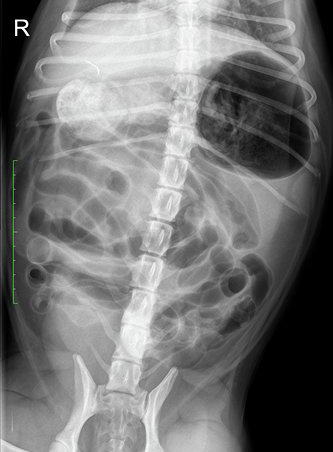

Het verhaal begint op het vakantieadres op Texel. Lady krijgt klachten van diarree, braken en ze is erg ziek. Bij de dierenarts worden vervolgens röntgenfoto’s gemaakt. Het is de verdenking dat ze ziek is geworden door het drinken van zeewater en het zand dat ze heeft binnengekregen, maar er is nog iets anders te zien; een langwerpige structuur.

Het baasje van Lady vindt het fijn als zijn eigen dierenarts ook naar de röntgenfoto’s kijkt en stuurt de foto’s naar ons. We staan zelf ook even te kijken over wat er op de foto te zien is. Ondertussen knapt Lady behoorlijk op en komt de eigenaar naar huis.

Ter controle, of de structuur nog in de buik aanwezig is, worden opnieuw röntgenfoto’s gemaakt. Hierop is het voorwerp nog goed zichtbaar, met een soort oogje erin. Het moet dus een naald zijn. De foto’s suggereren verder dat de naald niet in het maag-darmstelsel zit, maar in de buikholte.